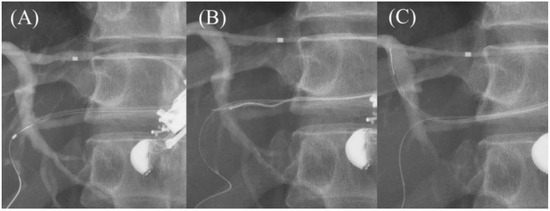

- Park, D.H.; Jeong, S.U.; Lee, B.U.; Lee, S.S.; Seo, D.W.; Lee, S.K.; Kim, M.H. Prospective evaluation of a treatment algorithm with enhanced guidewire manipulation protocol for EUS-guided biliary drainage after failed ERCP (with video). Gastrointest. Endosc. 2013, 78, 91–101. [Google Scholar] [CrossRef]